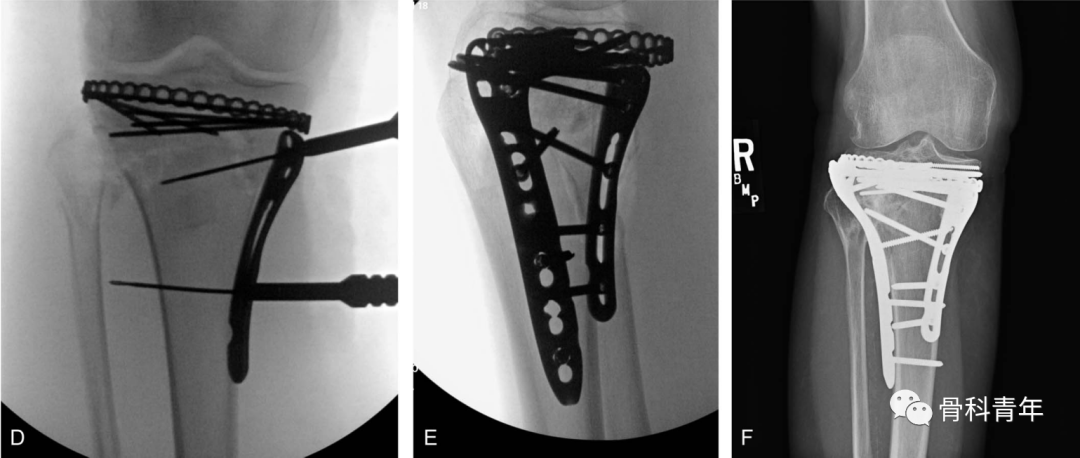

在复位满意后,将环形钢板塑形,通过平台后方建立的软组织隧道,穿出至外侧,并在外侧采用2枚2.7mm螺钉临时固定。

步骤4:点式复位钳拉紧环形钢板后,在内侧置入2枚2.7mm普通螺钉固定。关节面直视下及C臂机辅助下,评估复位情况及钢板位置情况。